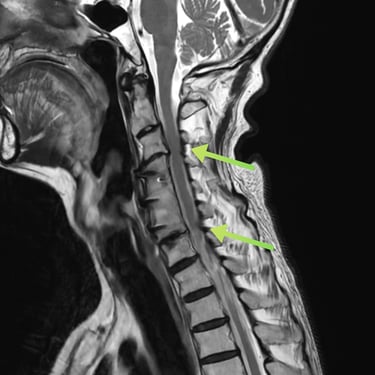

🧠 Cirugía de Revisión Cervical: Estabilidad Posterior en Seudoartrosis y Enfermedad del Segmento Adyacente.

La seudoartrosis cervical con subsidencia del cage y enfermedad del segmento adyacente genera dolor e inestabilidad. La artrodesis cervical posterior con tornillos a masas laterales y pediculares es una técnica eficaz para lograr una fijación sólida, mejorar la estabilidad y aliviar los síntomas neurológicos.